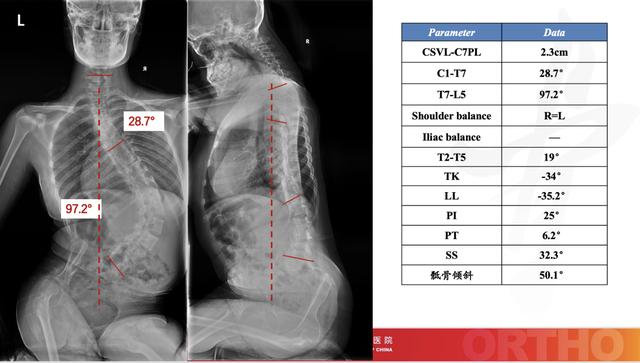

姗姗术前脊柱全长X线

朝阳骨科脊柱团队术前规划

武姗姗手术前后脊柱X光片对比